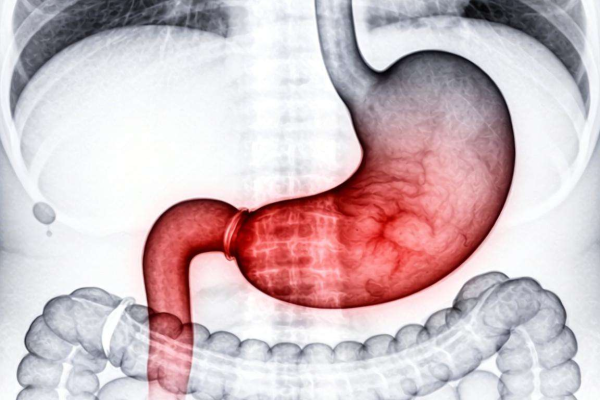

胃底充血水肿是一种在胃镜检查中较为常见的胃部异常状况,它往往意味着胃黏膜正处于炎症侵袭状态,反映出胃部的健康亮起了红灯。多种因素都可能导致胃底出现充血水肿,像长期不规律的饮食习惯,时而暴饮暴食,时而过度节食,或者频繁食用辛辣、生冷、性强的食物,都会对胃黏膜造成严重;烈酒、浓茶、咖啡等饮品的过量摄入也会加重胃黏膜的损伤;幽门螺杆菌感染更是引发胃部炎症的常见病因之一,这种细菌会在胃内大量繁殖,破坏胃黏膜的保护屏障,进而引发充血水肿等症状。当胃处于这种状态时,患者的胃部功能已经受到了不同程度的影响,消化能力下降,还可能伴有胃痛、胃胀、恶心、呕吐等不适症状。在这样的身体状况下,饮食和饮品的选择就显得尤为重要,任何不当的摄入都可能进一步加重胃部负担,影响病情的恢复。而红酒,作为一种含有一定酒精成分的饮品,对于胃底充血水肿的患者而言,是否能饮用自然成为了一个备受关注的问题。

从红酒的成分来看,它除了含有一定量的酒精外,还富含多种有益物质,如抗氧化剂、多酚类化合物等。这些成分在一定程度上具有保护心血管、延缓衰老等作用。对于胃底充血水肿的患者来说,酒精的性才是更需要关注的方面。酒精进入人体后,会直接与胃黏膜接触。即使是红酒中相对较低浓度的酒精,也会对已经处于充血水肿状态的胃底黏膜产生。它会破坏胃黏膜表面的黏液层,使胃黏膜失去这层重要的保护屏障,从而让胃酸更容易侵蚀胃黏膜,进一步加重炎症反应。原本就脆弱的胃底黏膜在酒精的下,充血水肿的情况可能会加剧,疼痛和不适的症状也会更加明显。